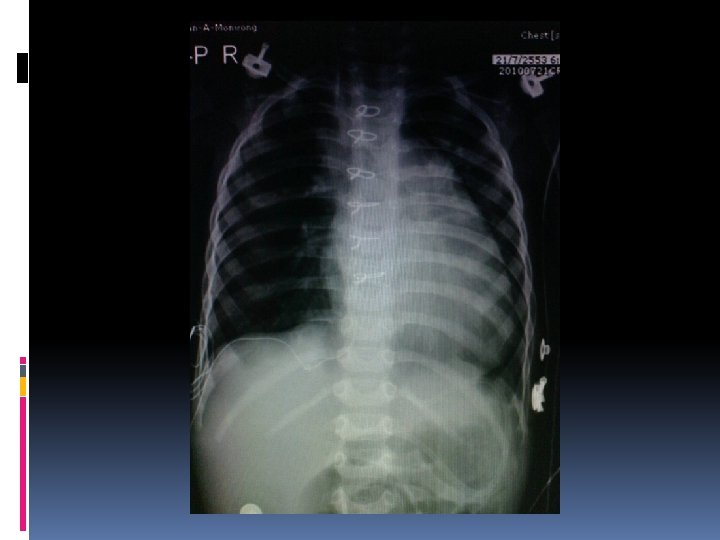

Case discussion: case I A male premature baby, birth weight 2. 1 kg Respiratory distress with heart murmur No dysmorphic feature Normal S 1, S 2 with SEM gr 2/6 at LPSB

Investigation Echocardiography Single functioning morphologic RV, DIRV, DORV, rudimentary LV, large bulboventricular foramen Mild MS, No AS, No PS hypoplastic aortic arch 3 mm, severe Co. A 2. 5 mm, PDA 3. 3 mm CTA heart

Operation and findings Severe coarctation of the aorta and hypoplastic aortic arch Hypoplastic LV Deep hypothermia + circulatory arrest Resection and end-to-end anastomosis Pulmonary artery banding